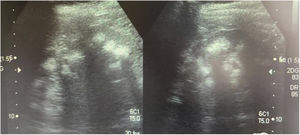

Caso 3La madre de los pacientes, de 29 años de edad, con antecedente de madre diabética y padre hipertenso en tratamiento. Hermano mayor con litiasis renal y episodios múltiples de parálisis flácida. Fue diagnosticada al realizar el abordaje diagnóstico de sus hijos. Con avidez por el agua desde la infancia. Su peso era 58kg, la talla 157cm y la presión arterial 100/60mmHg. Los niveles de creatinina eran 0,78mg/dl (CCr 122ml/min), el sodio 139mEq/l, el potasio 3,3mEq/l y la cloremia 113mEq/l. En la gasometría venosa se comprobó una acidosis metabólica (pH 7,17, HCO3− 14,1mEq/l) con hipocitraturia (14mg/24h) y proteinuria 382mg/24h (tabla 2). El pH urinario era 7 y el hiato aniónico (anión gap) urinario positivo (+36). En el ultrasonido renal se observó nefrocalcinosis medular grado II-III (fig. 3). Se comprobó la existencia de un cálculo en el tercio inferior ureteral derecho y otro de 1,5cm en la vejiga. Se realizó el estudio genético analizando los genes ATP6V0A4, ATP6V1B1 y SLC4A1. Se comprobó la presencia de una variante patogénica en heterocigosis en el exón 20 del gen SLC4A1, c.2710_*12, p. (Tyr904_Val911delins68) que se traduce en una deleción de 39 bases (27 del ultimo exón y 12 de la región 3’ UTR) que modifica la parte carboxi terminal de la proteína (deleción de los últimos 8 aminoácidos e inserción de una nueva secuencia de 68 aminoácidos). Esta variación no descrita en la literatura y no incluida en la base de datos, es considerada patógena, de acuerdo a la ACMG 2015, clase 5 (American College of Medical Genetics and Genomics); los criterios usados para clasificarla en clase 5 son: PVS1, PM2, PM1, PM4. Esta variación no está presente en la base de datos de población general gnomAD (criterio PM2)

Ecografía realizada a la madre de los pacientes. Riñones con ecogenicidad heterogénea a expensas de un aumento de la ecogenicidad de las pirámides renales compatible con nefrocalcinosis medular bilateral grado II-III. La relación córtico medular es poco nítida, con datos de nefropatía crónica difusa.